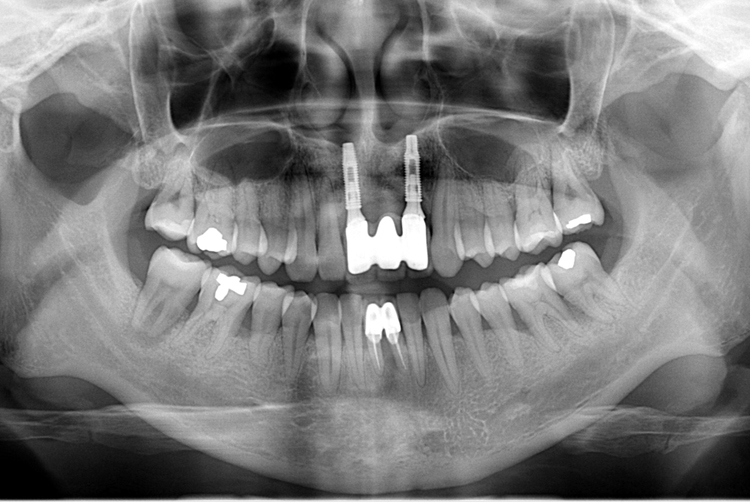

[임플란트] 앞니 임플란트

치료전 : 2019-09-18

치료후 : 2019-11-29

세종치과는 많은 환자와 다양한 케이스를 바탕으로

항상 편안한 임플란트 수술을 제공하고자 노력하고,

오래동안 튼튼히 쓸 수 있는 임플란트 수술을 가장 큰 목표로 삼고 있습니다.